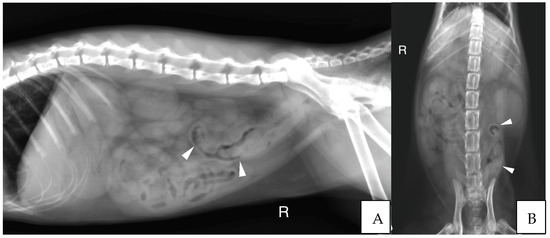

3.2.3. Abdominal Radiographs